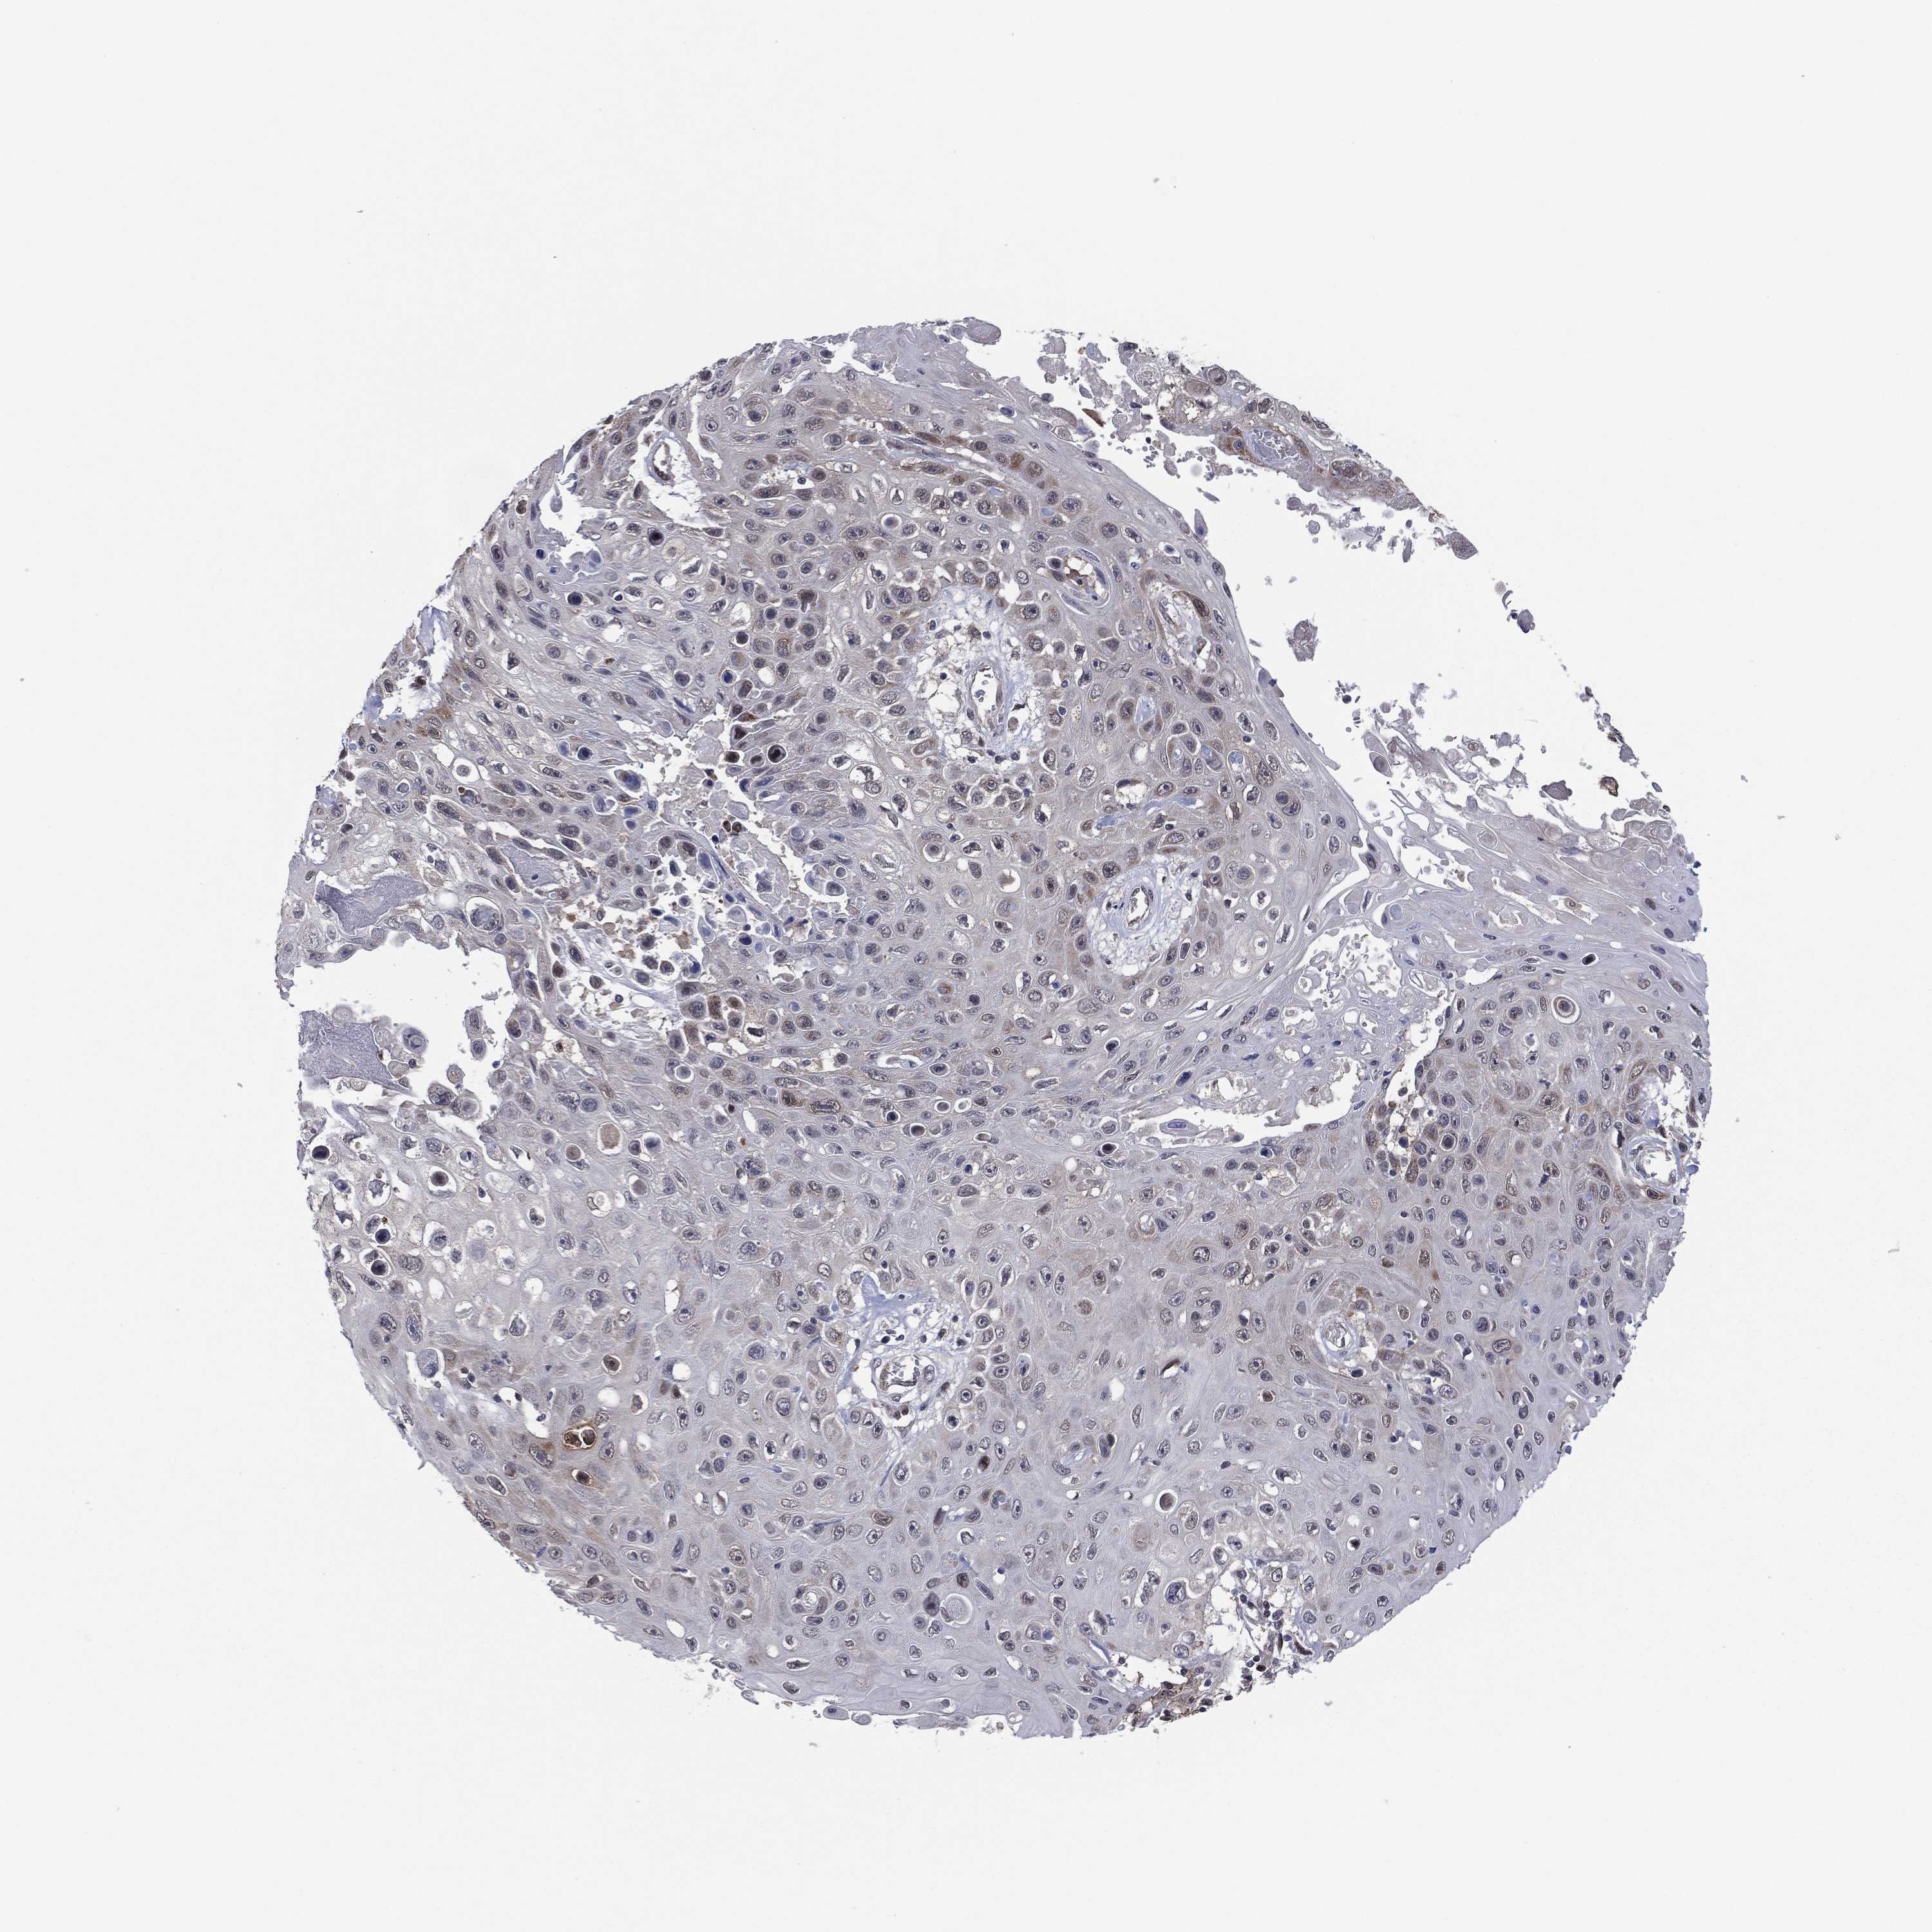

SKIN CANCER - Protein expressioni

A mouse-over function shows sample information and annotation data. Click on an image to view it in a full screen mode. Samples can be filtered based on level of antibody staining by selecting one or several of the following categories: high, medium, low and not detected. The assay and annotation is described here.

Each image is clickable and will lead to virtual microscopy that enables deeper exploration of all samples and also displays staining intensity scores, fraction scores and subcellular localization as well as patient and tissue information for each sample.

Antibody CAB080022

Squamous cell carcinoma, metastatic, NOS